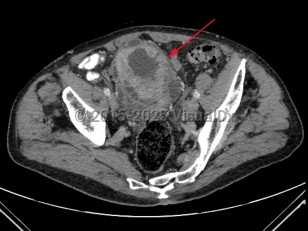

Bladder cancer

Treatment options depend on depth of tumor invasion and presence or absence of metastatic disease. Transurethral resection of bladder tumor (TURBT) may be combined with adjuvant chemotherapy for early-stage disease with radical cystectomy and/or chemotherapy in late-stage disease.